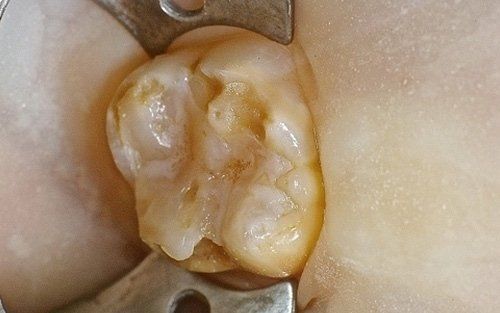

Despite the first signs having been noticed by practitioners at the end of the last century, we can consider the hypomineralisation of molars and incisors (M.I.H. - Molar Incisors Hypomineralisation) as a condition of children in the 2000s. It is characterised by insufficient mineralisation, especially of the first permanent molars, which appear with white-yellowish or brown spots and enamel that is very "porous," lacking the protective shield necessary for the health of these teeth. This leads to a greater tendency for decay, but above all, to structural breakdown of the affected areas under chewing load.